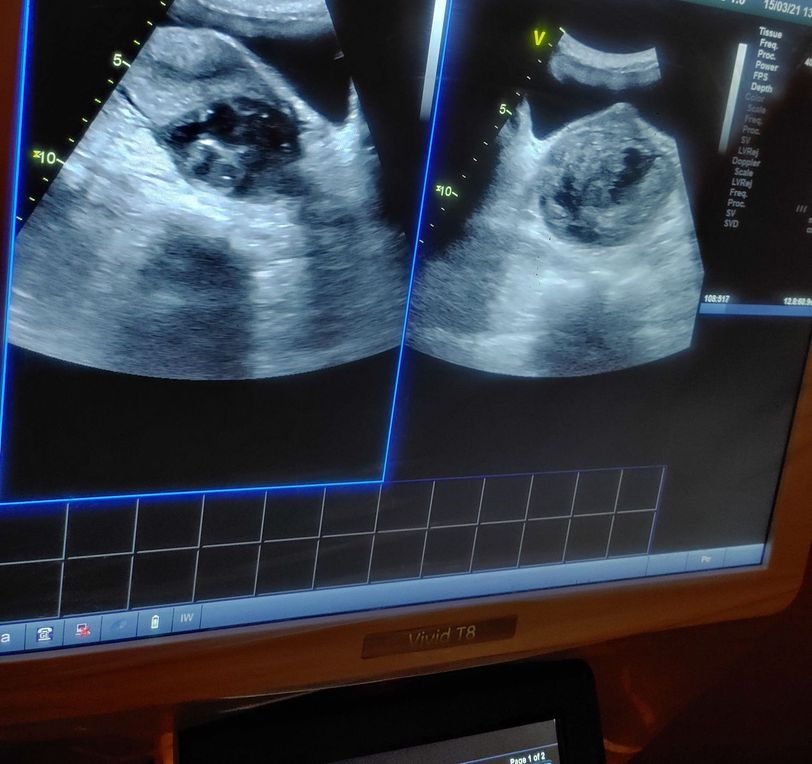

Female of age complaining stomach pain came to hospital doctor done ultra sound abdomen it results fibroids in abdomen

Abdomen

Fibroids